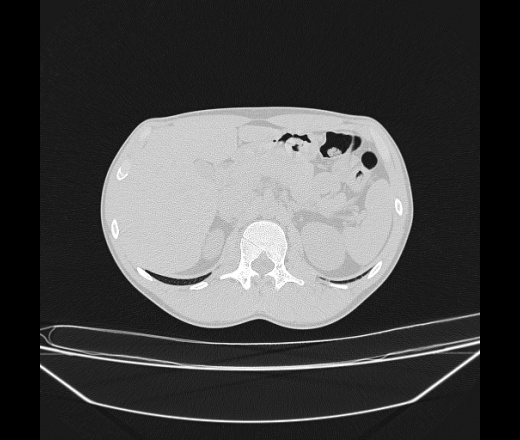

Молодой парень 18 лет, призывник, при прохождении ФЛС на верхушек левого легкого выявили очаги средней интснисвности с нечеткими контурами, тяжи. Сделали бок и томограммы 6-7-8. Везде описывают как очаговый твс. Вижу только перибронхиальный фиброз. Что за изменения в бронхах, указано нижи стрелками, тоже перибронхиальный?